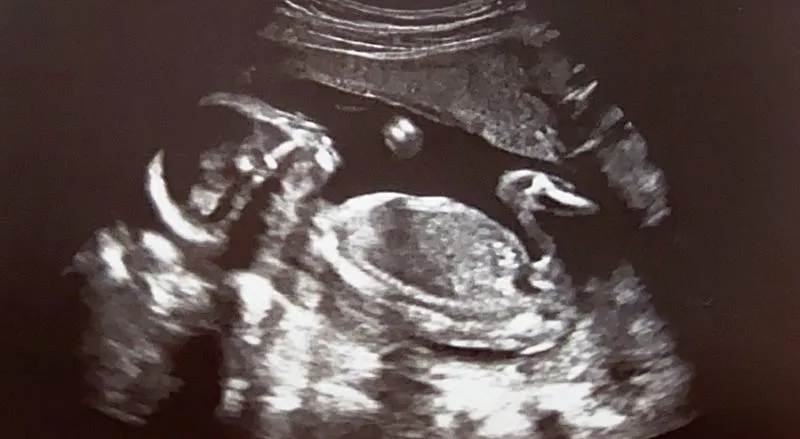

我記得第一次產檢的時候,在超音波上第一次看到了他,感動地忍不住就濕了眼框,原來這就是當爸爸的感覺。

現在已經五個月,我每天都摸著 Vicky 越來越圓的肚子,想著媽媽什麼時候會比爸爸胖呢?(揍飛)